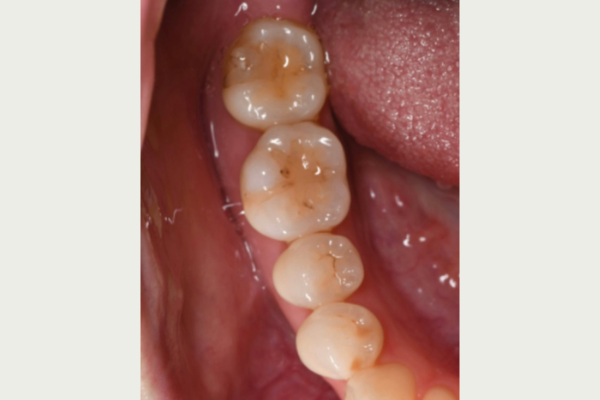

左上奥歯のセラミックインレー。

| 主訴 | インレー見た目気になる 左上67 |

| 治療内容 | 左上67セラミックインレー |

| 治療費 | 110,000円 (セラミックインレー1本55,000円) |

| 治療期間 | 約1~2週間 |

| リスク・副作用 | 稀に割れることがある 凍みることがある 再度虫歯になる可能性がある |